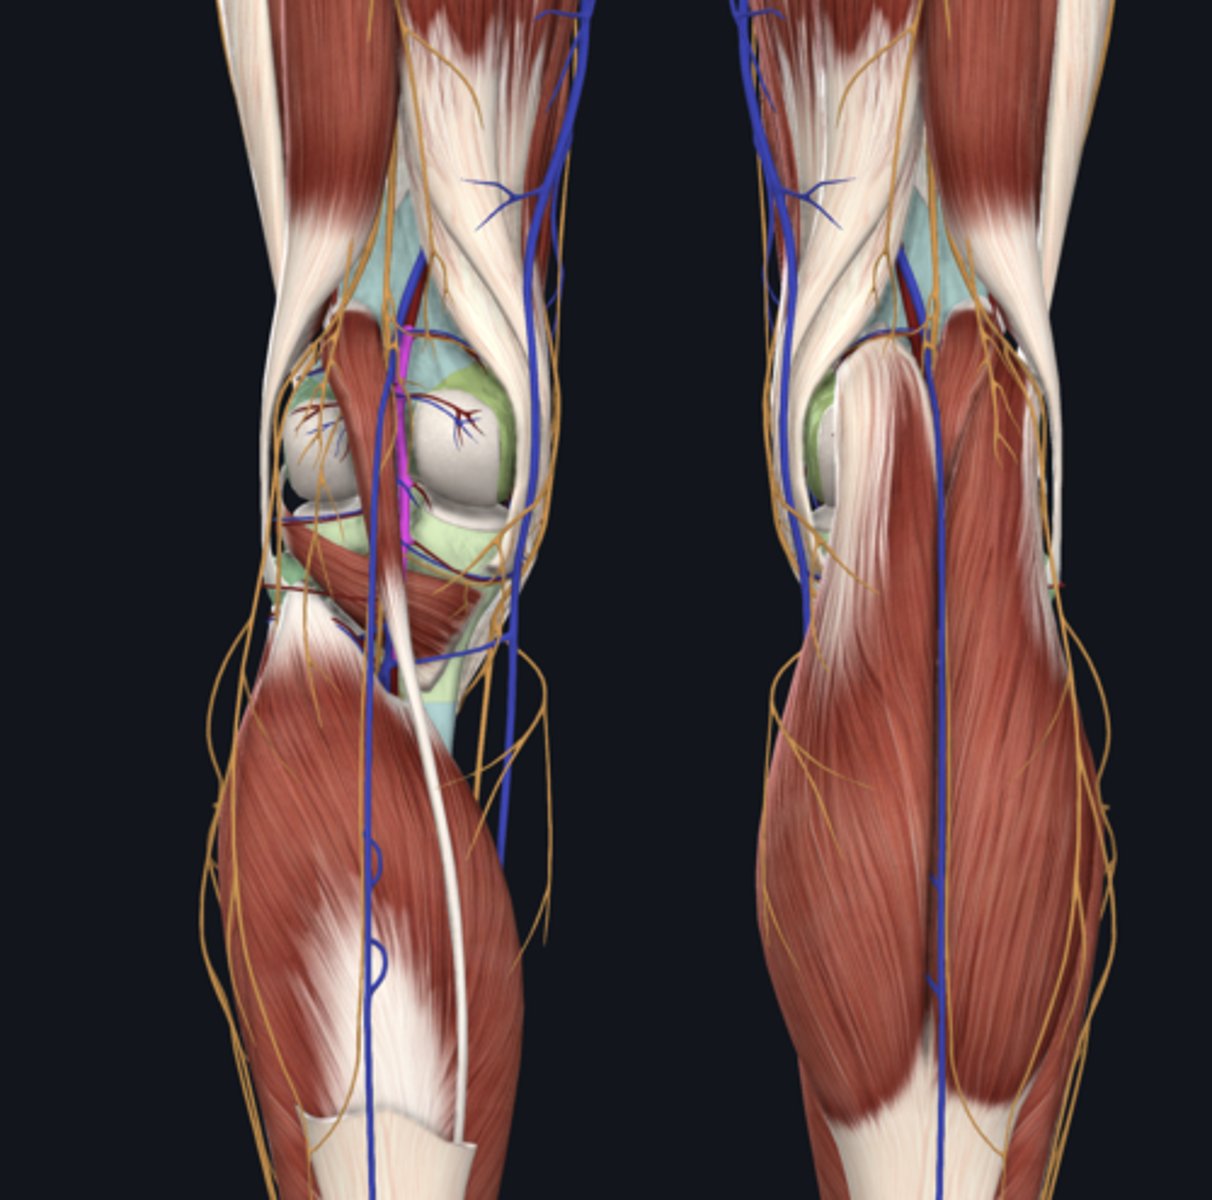

Popliteal artery

artery

Popliteal vein

vein

Tibial nerve

nerve

Medial head of gastrocnemius

Lateral head of gastrocnemius

Soleus

Plantaris